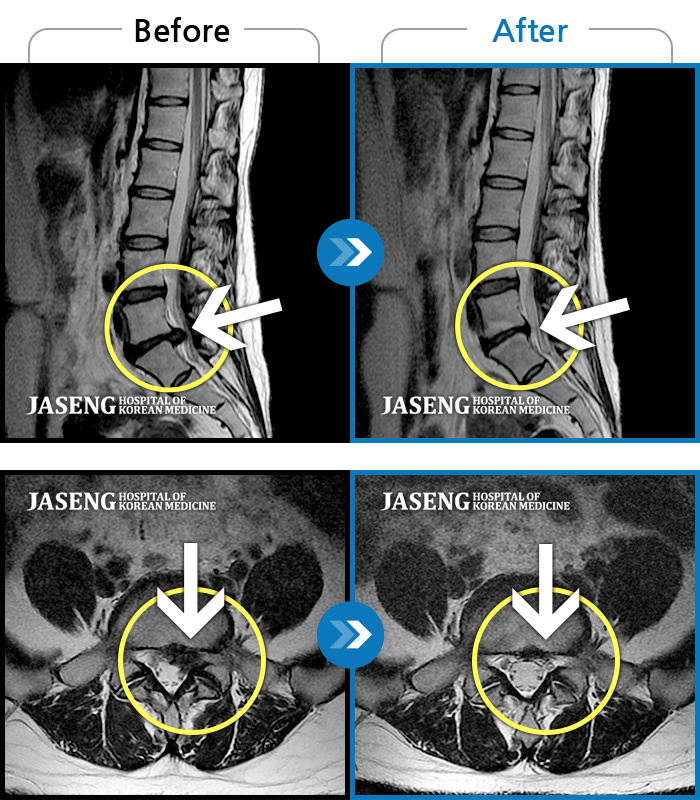

Before

After

허리 통증과 우측 허벅지 통증 및 저림 증상 지속되어 내원하셨습니다.

2022.08.20 ~ 2024.11.08